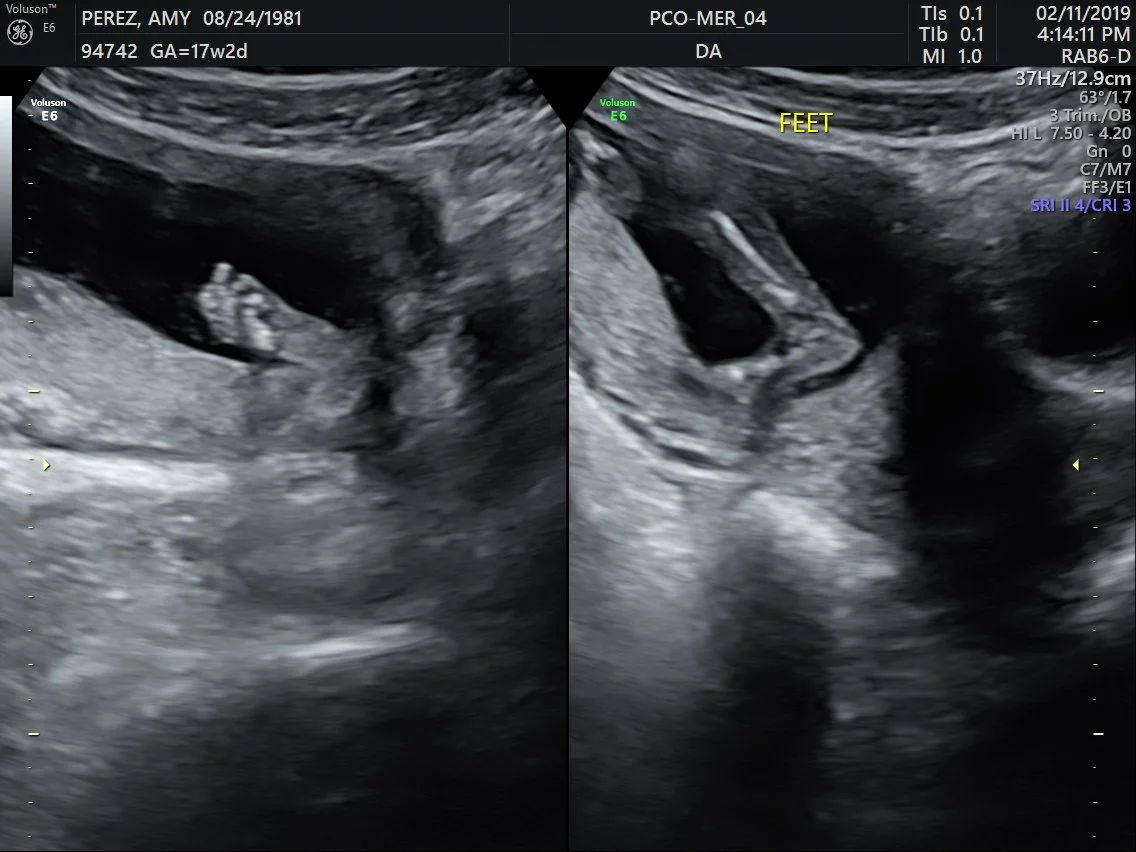

SONOGRAM #2

IT’S A GIRL!!! We had our 16 week sonogram appointment earlier this week and everything went very good. There is no real meaning or story behind her first name Pressa but it was just something we thought of a couple years ago. Her middle name Eve is a shortened version of Amy’s late brother’s middle name Everette.